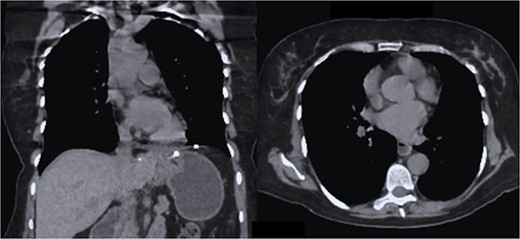

The case is reported of a 52-year-old woman, without significant illnesses, who presented with non-specific chest pain for 1 year, 6 months later with intermittent episodes of dyspnea with great and medium exertion, dysphagia, and heartburn. During the examination, hypoventilated lung fields at the bases, peristaltic sounds, and tympanism on percussion were heard. The thoracoabdominal tomography with contrast shows a diaphragmatic hernia containing the stomach, portions of the duodenum, pancreas, small intestine, and colon (Fig. 1), with a sac measuring up to 20 cm (Fig. 2).

CT in axial section, hernia sac measuring ~21 × 15 × 7 cm is observed.